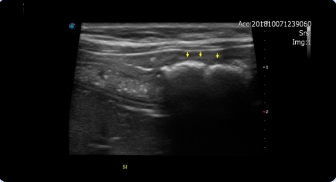

심장 초음파

호흡곤란, 운동 불내성, 기절과 같은 임상증상을

보이는 경우

심장초음파 검사가 필요 할 수 있습니다.

동맥관개존증

이첨판폐쇄부전

심장사상충증